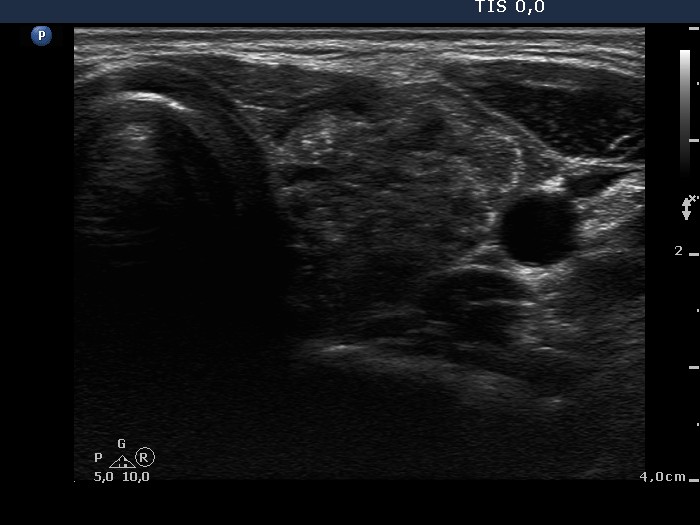

Papillary carcinoma (histological diagnosis) - case 469 |

![]() |

This tumor contained numerous punctate echogenic foci (microcalcifications). |